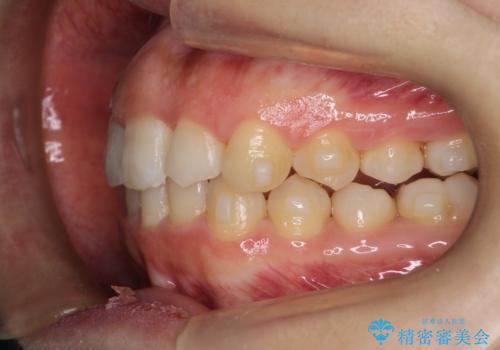

押しつぶされた歯列、アーチの拡大だけで非抜歯で改善した症例

強い叢生がありましたが、抜歯は行わず上下顎ともに、主に歯列弓の拡大を行い叢生を改善しました。

見た目、嚙み合わせ及び、治療期間や施術内容に大変ご満足いただきました。